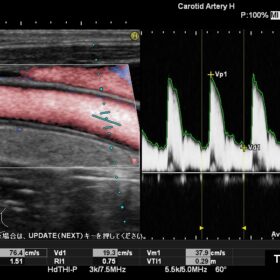

Radiology 2D, Color, PW and Elasto mode

The Ultra BE, an ultrasound-specific digital signal processor is at the core of the Noblus. Achieving advanced beam formation and sophisticated image processing. Migrated from the high-end HI VISION cart-based systems, this technology brings reliable diagnostic performance. That will ensure a smooth workflow. It’s powerful transmission and reception capability enables functions. Such as Real-time Tissue Elastography (RTE) and dynamic Contrast Harmonic Imaging (dCHI), modalities that can offer increased diagnostic confidence.

Reliable performance for enhanced workflow

Using Hitachi’s own broadband technology to increase the harmonic frequency bandwidth, the High definition dynamic Tissue Harmonic Imaging (HdTHI) mode gives you both high resolution and excellent penetration. The HI Rez+ tissue adaptive filter optimises contrast resolution, border enhancement and noise suppression without reducing frame rate, and the HI Com, real-time spatial compounding technology, that uses multiple beams on transmit and receive, is especially beneficial for clarifying luminal structures

The Noblus offers premium modalities that can be exploited in many different clinical situations. Although compact in design, the powerful engine of the Noblus enables functions such as Real-time Tissue Elastography (RTE), dynamic Contrast Harmonic Imaging (dCHI), real-time 3D with STIC (Spatio-temporal Image Correlation) option and CW Doppler, features previously found only on larger cart-based systems.